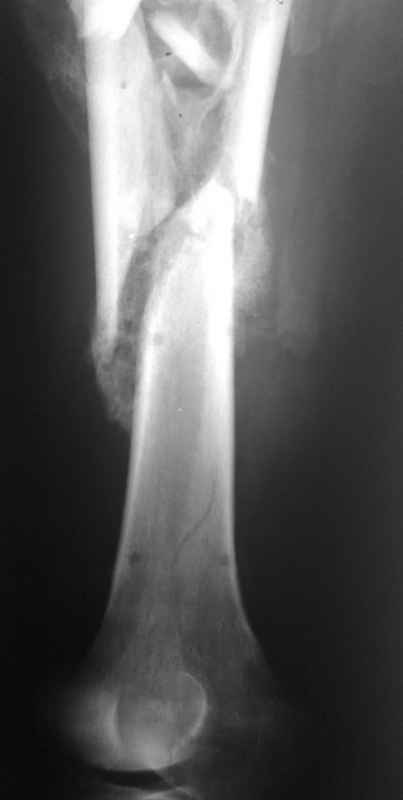

[Ortho] Неправильно срастающийся оскольчатый перелом бедра

Вложение не в текстовом формате было извлечено…

Имя     : 002.jpg

Тип     : image/jpeg

Размер  : 13116 байтов

Url     : http://weborto.net:8080/pipermail/ortho/attachments/20110406/c06e2959/attachment-0005.jpg